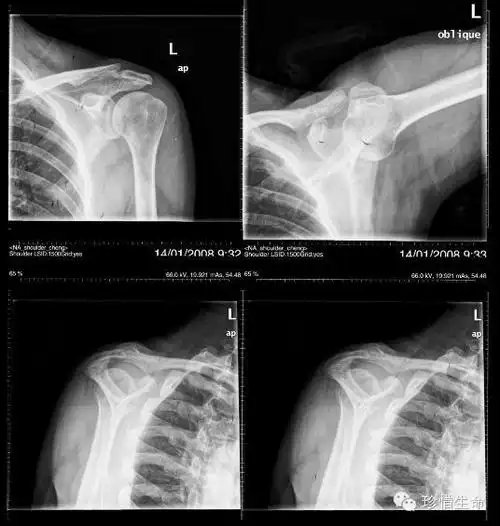

肩关节正位-x线图

中年女性,发现右肩关节占位2天.有特征,有细节---(有结果)

术后右肩关节正位片